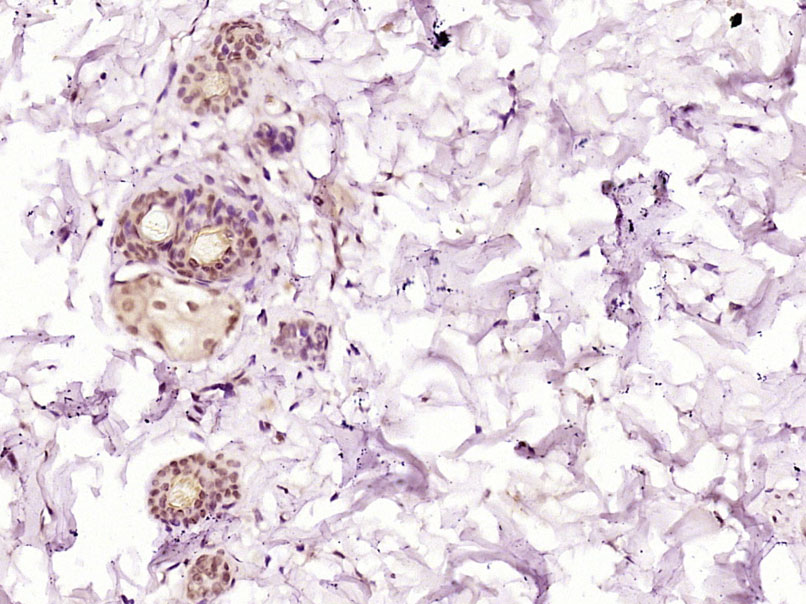

Paraformaldehyde-fixed, paraffin embedded (Human skin); Antigen retrieval by boiling in sodium citrate buffer (pH6.0) for 15min; Block endogenous peroxidase by 3% hydrogen peroxide for 20 minutes; Blocking buffer (normal goat serum) at 37°C for 30min; Antibody incubation with (ZZZ3) Polyclonal Antibody, Unconjugated (bs-16387R) at 1:500 overnight at 4°C, followed by a conjugated secondary (sp-0023) for 20 minutes and DAB staining.